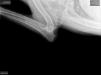

OFA hips and elbows 11.13.18 : SG1 Pyro vom Julianenweg OFA good hips normal elbows 2019 Green Mountain Iron Dog